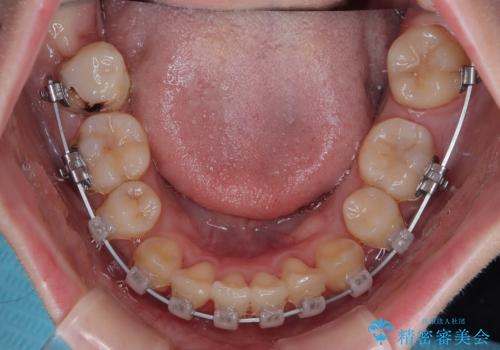

上下の八重歯とクロスバイト ワイヤー装置での抜歯矯正

- 八重歯とクロスバイトを気にして来院された患者様です。

上下ともに八重歯が顕著であり、前歯のクロスバイトがあったため、上下左右の第一小臼歯4本を抜歯し、ワイヤー装置での抜歯矯正を行うこととしました。